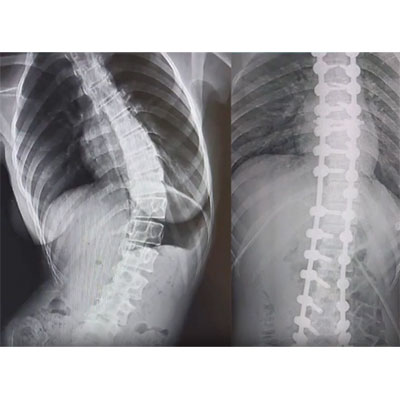

Skolyoz, omurganın yandan bakıldığında S veya C şeklinde eğrilik gösterdiği bir omurga hastalığıdır. Genellikle çocukluk ve ergenlik döneminde başlayan bu durum, omurganın düzgün hizalanmasını engeller. Skolyozun nedeni tam olarak bilinmese de, çevresel, genetik veya nöromüsküler faktörlerle ilişkili olabileceği düşünülmektedir. Hafif vakalardan ciddiye kadar değişen şiddette görülebilir ve bazı durumlarda belirti vermeden ilerleyebilir. Ancak ilerleyen vakalarda, omurga eğriliği ve eşlik eden postür bozukluğu nedeniyle fiziksel rahatsızlıklara, sırt ve bel ağrısına, solunum güçlüklerine ve organlara baskıya neden olabilir. Erken teşhis ve tedavi, skolyozun ilerlemesini engellemeye ve yaşam kalitesini artırmaya yardımcı olabilir.

İşlem Görüntüleri

Omurganın ön ve arkadan bakıldığında 8 - 10 derece üzerindeki sağ veya sol tarafa olan eğriliği ile buna eşlik eden, kendi ekseni etrafındaki dönme hareketinin (rotasyon ) oluşturduğu bir şekil bozukluğudur. Skolyoz omurga deformiteleri içerisinde en sık karşılaştığımız ve ilerleyen evrelerde ciddi duruş bozukluklarına neden olan üç boyutlu bir omurga deformitesidir.